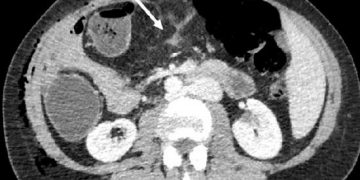

Yağ infiltrasyonu, vücudun bilinen belli yerleri dışında yağın birikmesi veya infiltrasyonu haline denir. Fat infiltration